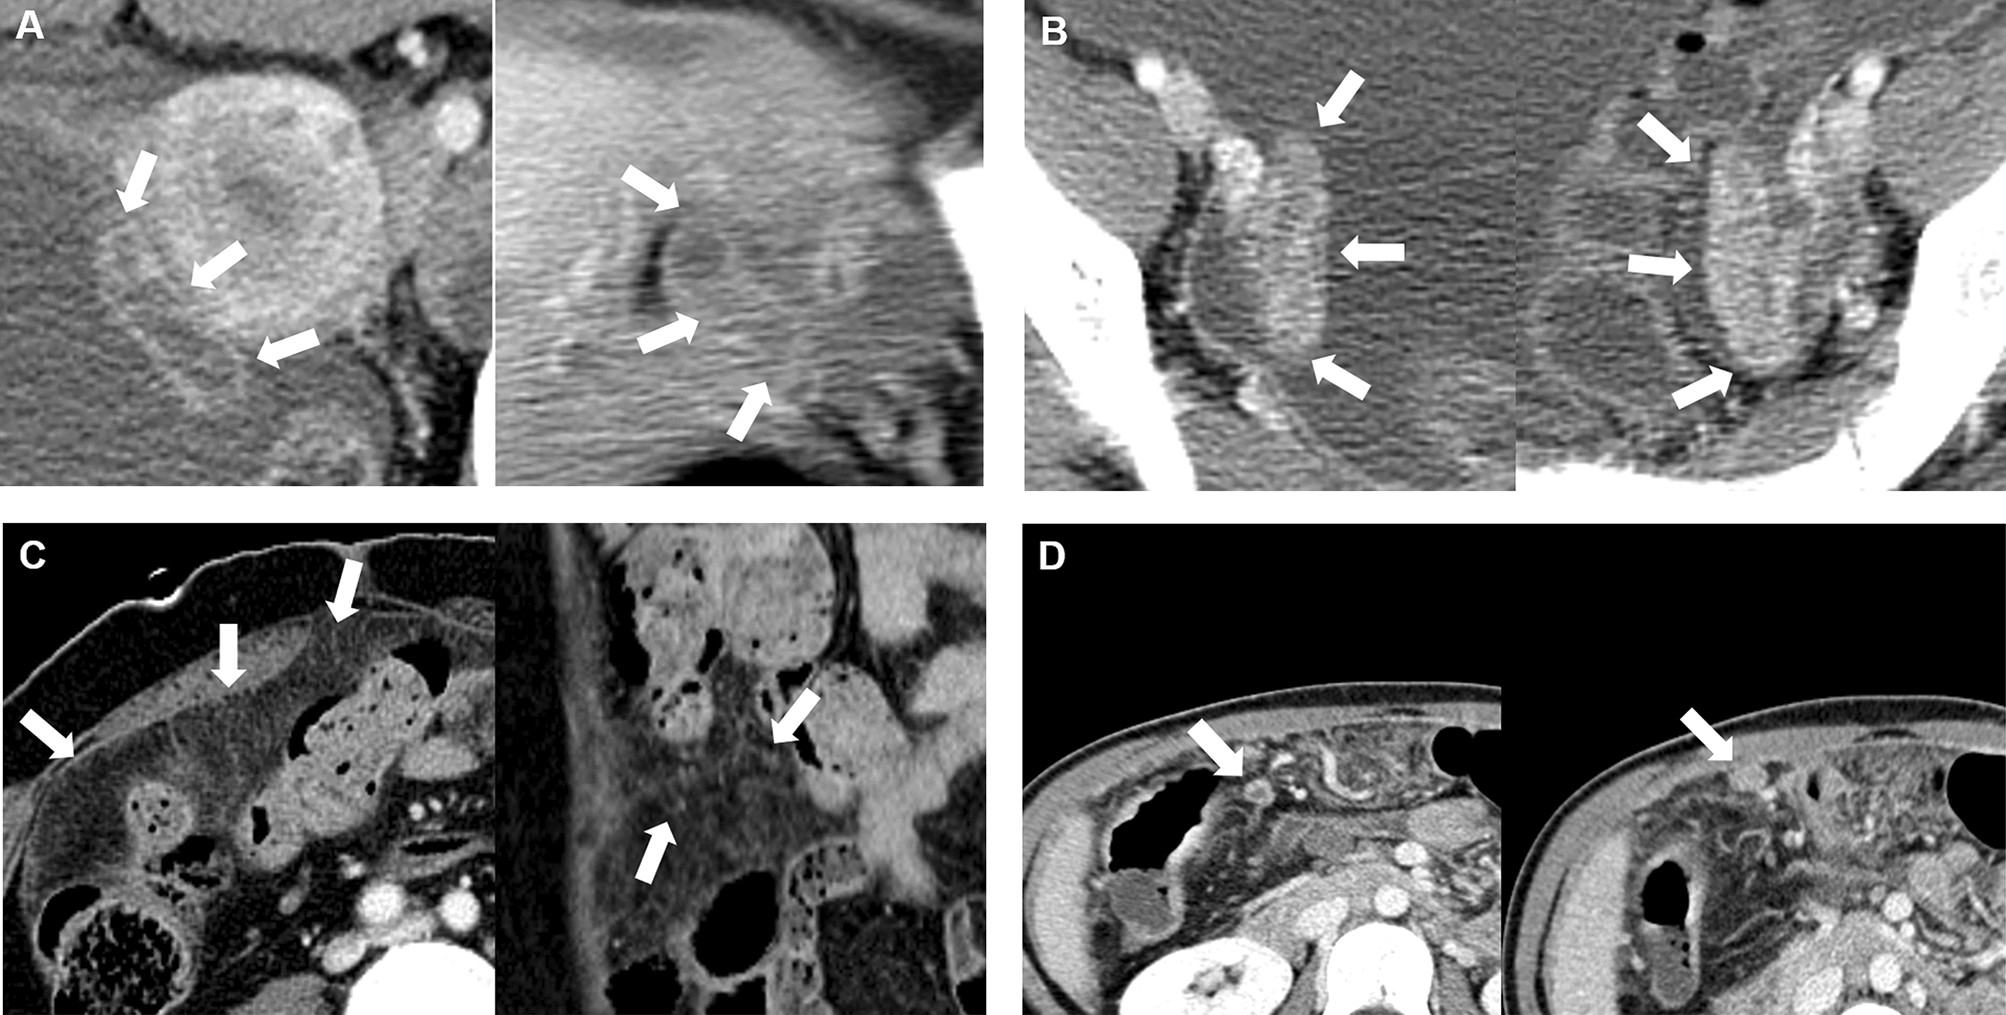

Representative cases of CT imaging features. (A) Hydrosalpinx, (B) fallopian tube enhancement, (C) peritoneal micronodule, and (D) peritoneal macronodule.